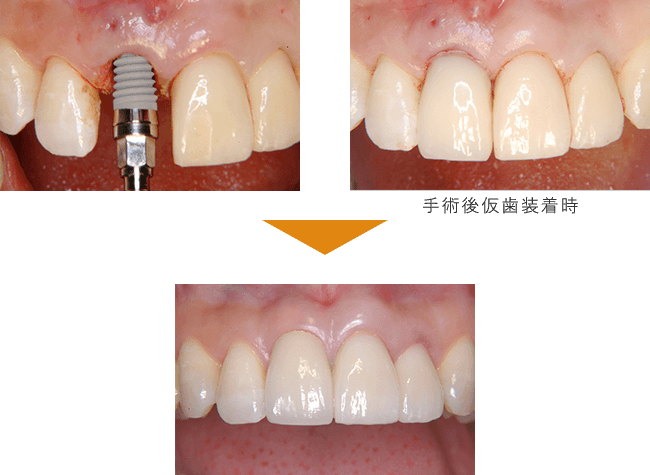

症例紹介

症例1

単独歯 インプラント即時荷重

| 治療期間 | 約4カ月 |

| 費用 |

インプラント治療費 400,000円

造骨費用 50,000円

合計 450,000円(税込) |

※状態により、骨補填等別途で費用が発生する場合もございます。